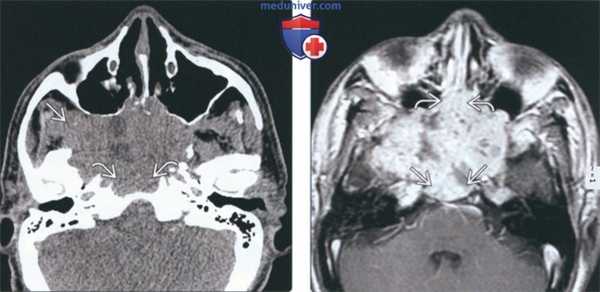

(Слева) На аксиальной КТ без КУ в сфеноидальных пазухах определяется большое мягкотканное образование неоднородной плотности, распространяющееся кнаружи в правую подвисочную ямку и кзади в скат. Картина типична для поздней стадии Т синоназального аденокистозного рака (АКР).

(Справа) На аксиальной MPT (Т1 ВИ С+) у этого же пациента определяется диффузное неоднородное контрастирование опухоли с обширной инвазией ската и распространением в полость носа.